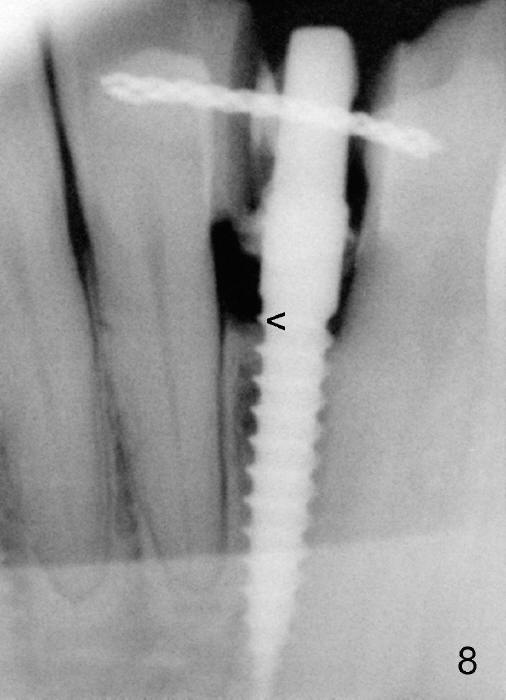

Informed consent is obtained with emphasis of potential damage to the neighboring roots.  Two PAs have to be taken with the first pilot drill (1.5 mm) in place for determination of initial trajectory (Fig.2,3).  Osteotomy is enlarged coronally with 2 mm pilot drill.  Finally a 3x17 mm one piece implant is placed with primary stability, determined tactilely (Fig.4).  Immediate provisional is fabricated.  To avoid micromovement, the immediate provisional (Fig.5 P) is bonded to the neighboring teeth with composite (*); it is further fixed in place with a lingual retainer (Fig.6 arrowhead).

Within the first several days postop, the patient reports mild tenderness from one of the neighboring teeth.  Otherwise she is doing fine.  Again due to finance, she does not return for restoration for more than 1 year.  PA taken 10 months postop shows that there is no abnormality (Fig.7).  In fact bone resorption occurs gradually over 2 years 2 months postop, manifested as the 1st thread supracrestal (Fig.8 <).  When the 1-piece implant is reprepped for impression 2 years 2 months postop, the micro threads are found apical to the prep margin (Fig.9).  The nervous patient has had occasional tooth sensitivity 5 years postop.  A narrower implant is more suitable for this case (2.0 or 2.5 mm).